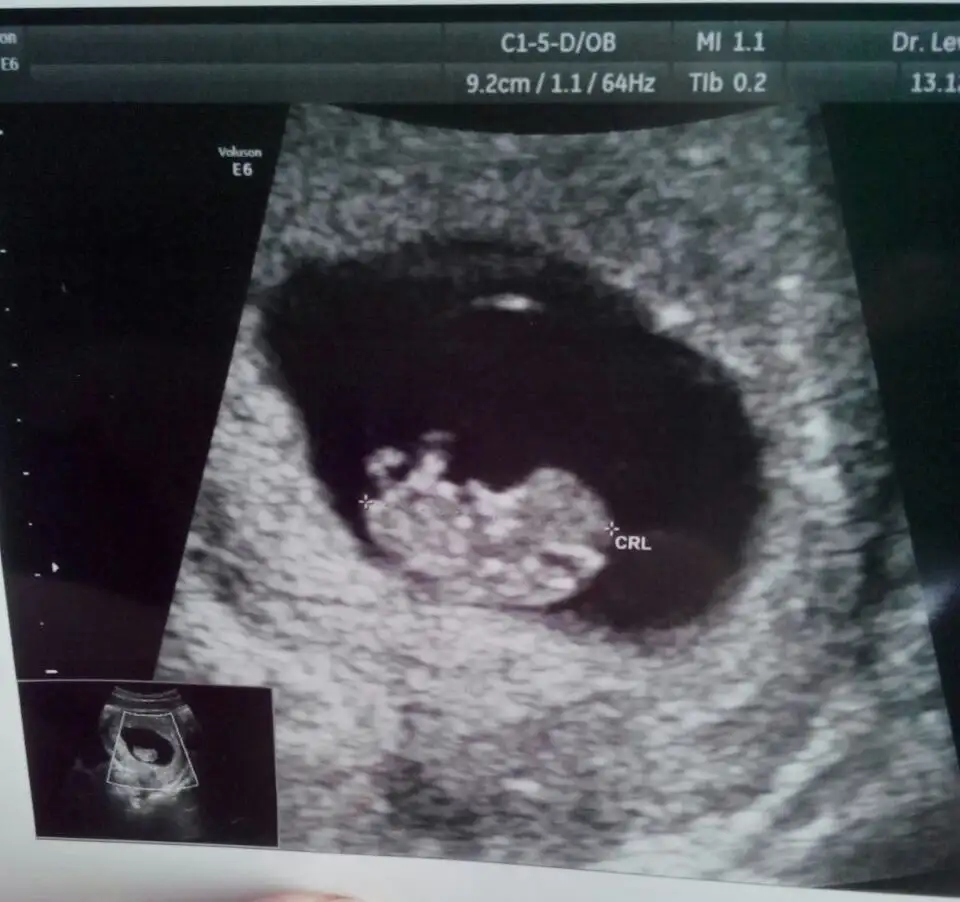

baktım ama popodaki + işaretinin olduğu yere nub dersek kız gibi, başka çıkıntı göremedim. senin de kafanı karıştırıyoruz bi kız bi erkek diye ama..![]()